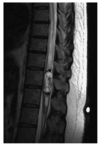

Which one of the following is most likely based on the T2-Weighted MRI shown below?

a. Ependymoma

However, studies have shown that ependymomas

have a predilection for the caudal spinal cord,

with 50% of ependymomas arising in the lumbosacral cord or filum terminale and the remaining 50% occurring nonpreferentially along the cervical or thoracic spinal cord. On imaging, anaplastic ependymomas may be distinguished by their larger size, numerous cysts, and heterogeneous postcontrast enhancement. Anaplastic ependymomas are uncommon, comprising only 5% of all ependymomas, but they are characterized by anaplastic features (i.e. vascular proliferation, mitotic figures, cellular pleomorphism, and necrosis) on histologic analysis. Patients experience higher rates of tumor recurrence and decreased rates of survival. Classic radiographic features of spinal cord ependymomas include distinct tumor-spinal cord border, an associated syrinx, cysts within or adjacent to the mass, and hemosiderin deposits or “caps” near the poles of the tumor on T1 and T2. The treatment of

choice is gross total surgical resection.

A 34-year-old male presents with a several month history of neck pain, with intermittent episodes of arm and leg numbness. MRI is shown. Which one of the following is most likely?

Ependymomas arise from ependymal cells and

typically occur in the central canal of the spinal

cord, the filum terminale, and the white matter

adjacent to a ventricular surface. They are the commonest intramedullary spinal cord tumor in adults and commoner in males than females (the commonest intramedullary tumors in children are

astrocytoma, ganglioglioma then ependymoma).

The mean age at presentation is 30-40 years with

long duration of symptoms (e.g. 2-4 years). Two

thirds occur in the lumbosacral region (40% of

these arise from the filum terminale (myxopapillary ependymoma). Because of the propensity of these tumors for seeding the craniospinal axis,

CSF evaluation and MRI of the whole craniospinal axis is strongly recommended. The three

main subsets of ependymomas are cellular (this

case), myxopapillary, and anaplastic. Cellular

ependymomas are most often located in the cervical spine. On T1-weighted MRI, they are isointense to hypointense, whereas on T2-weighted MRI, they are hyperintense and there may be a syrinx in 50% of cases. Factors prognostic for a favorable outcome include patient age younger than 40 years; tumors with a lumbosacral location, myxopapillary histologic findings, or a grade of WHO grade I; tumors amenable to GTR or

STR; and good preoperative function of the

patient. Whether volume of residual disease

correlates with a worse outcome after EBRT is

controversial. Most intradural extramedullary

ependymomas are myxopapillary and are often

amenable to complete surgical resection if they

are not multifocal. The goal of surgery is GTR.

Every attempt should be made to remove tumors

as a whole as opposed to piecemeal removal,

because of the risk of seeding, including upward

seeding to the cranial nerves. Typically, complete

resection is achievable in 80-100% of modern

series, with 10-year survival for all spinal cord

ependymomas is 70-100%. Postoperative EBRT

appears to improve local control in patients with

STR ependymomas and also for patients with

high-grade lesions and those with neuraxis dissemination. In most but not all series, the outcome for STR followed by EBRT appears to be

similar to that of complete resection. In patients

with tumors at high risk of seeding, when pretreatment CSF cytologic studies reveal malignant cells, or if the spinal MRI scan shows evidence of leptomeningeal disease, the craniospinal axis should be

treated. There is no strong body of evidence

thus far demonstrating that the addition of

chemotherapy to EBRT improves the outcome,

but it is used in pediatric patients with anaplastic

ependymoma or ependymoblastoma are routinely

given chemotherapy